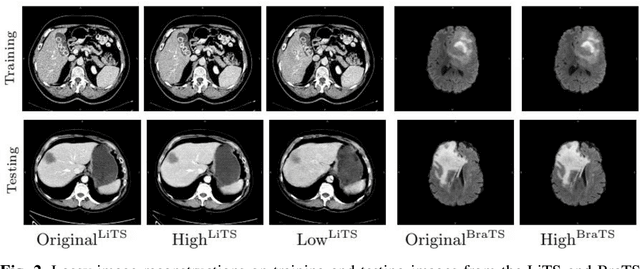

In privacy-preserving machine learning, it is common that the owner of the learned model does not have any physical access to the data. Instead, only a secured remote access to a data lake is granted to the model owner without any ability to retrieve data from the data lake. Yet, the model owner may want to export the trained model periodically from the remote repository and a question arises whether this may cause is a risk of data leakage. In this paper, we introduce the concept of data stealing attack during the export of neural networks. It consists in hiding some information in the exported network that allows the reconstruction outside the data lake of images initially stored in that data lake. More precisely, we show that it is possible to train a network that can perform lossy image compression and at the same time solve some utility tasks such as image segmentation. The attack then proceeds by exporting the compression decoder network together with some image codes that leads to the image reconstruction outside the data lake. We explore the feasibility of such attacks on databases of CT and MR images, showing that it is possible to obtain perceptually meaningful reconstructions of the target dataset, and that the stolen dataset can be used in turns to solve a broad range of tasks. Comprehensive experiments and analyses show that data stealing attacks should be considered as a threat for sensitive imaging data sources.